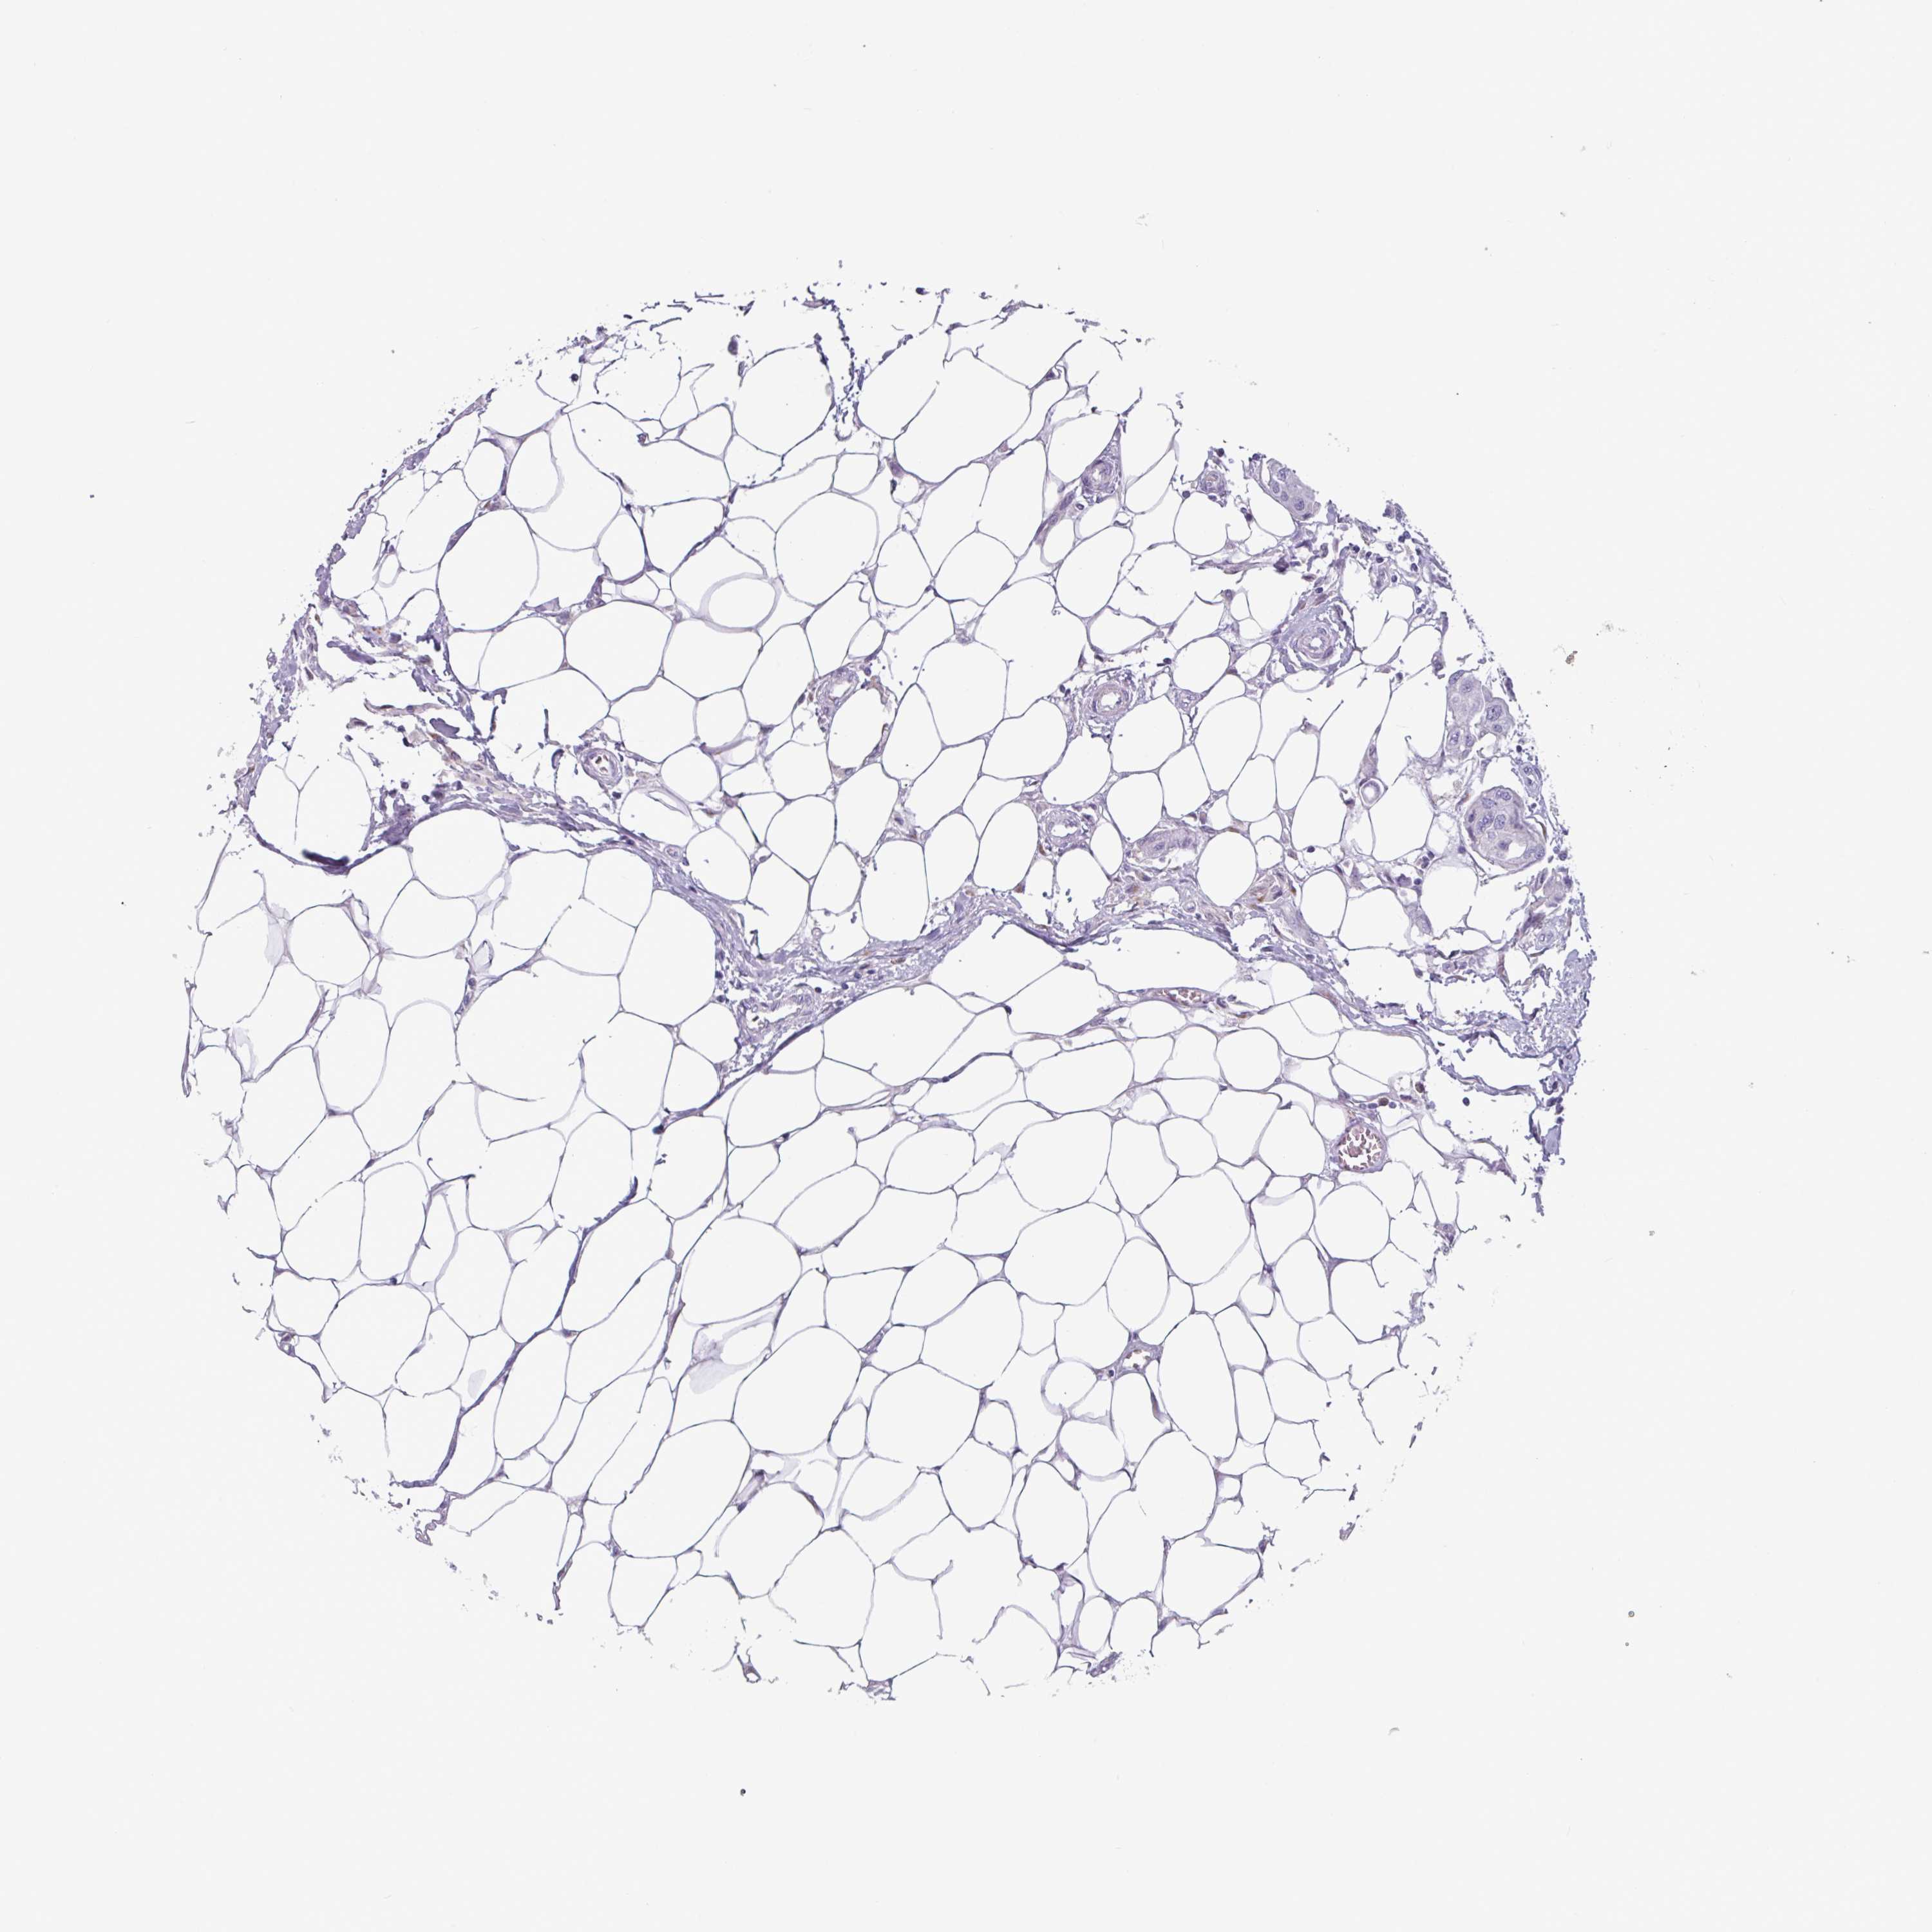

Breast cancer

Human cancer

Average pTPM 0.7

Number of samples 1022